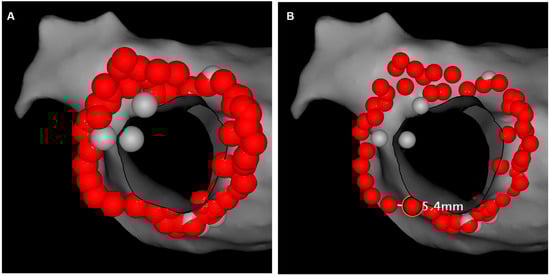

2.4. Postprocedural Assessment of Interlesion Distance